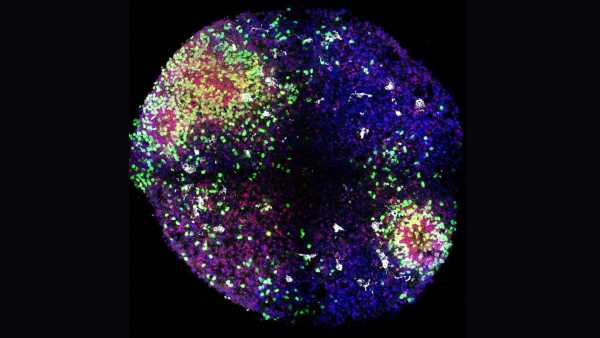

«Мінімозки» розкривають секрети формування ключових клітин мозку в утробі матері

«Мінімозки» розкривають секрети формування ключових клітин мозку в утробі матері

«Мінімозки» розкривають секрети формування ключових клітин мозку в утробі матері